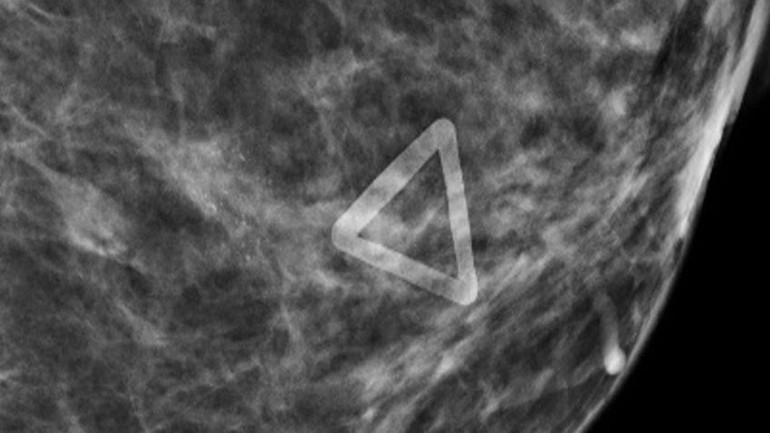

| Hình ảnh ung thư vú (vùng hình tam giác) được phóng to trên phim chụp X-quang 3D. |

Cho tới khi, tại Bệnh viện Đa khoa Tâm Anh Hà Nội, với kỹ thuật chụp X-quang vú phân giải cao, chị được phát hiện có vùng tổn thương 3mm ở ngực trái. Kết quả chụp X-quang 3D cho thấy đây là tổn thương ác tính.

Bác sĩ chuyên khoa II Lê Nguyệt Minh, Trưởng đơn vị Kỹ thuật cao, Bệnh viện Đa khoa Tâm Anh Hà Nội đã tiến hành sinh thiết tổn thương dưới hướng dẫn của X-quang. Kết quả xét nghiệm cho thấy ung thư biểu mô ống tại chỗ độ I, giai đoạn sớm. Bệnh nhân được phẫu thuật cắt bỏ toàn bộ vú trái, sức khỏe ổn định.